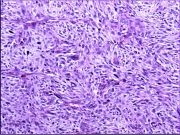

| 2021年12月10日 (五) 13:15 | 13号切片-纤维瘤-镜下观1.jpg (文件) |  |

174 KB | Cirno.9 | 基于MsUpload的文件上传 | 1 |